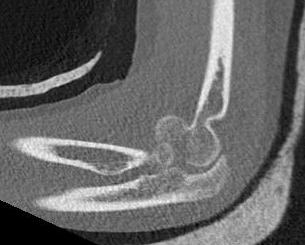

Dubberly Classification

| Type I | Type Ii | Type III |

|

Capitellar fracture

Capitellum + trochlea fracture In one piece Double arc sign seen on xray |

Capitellum + trochlea fractures In two separate pieces |

Double arc sign on xray |